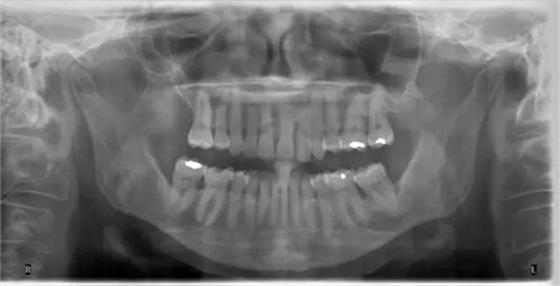

圖 6 全景片,清晰顯示關(guān)節(jié)。另外對牙列有大致概念,但對細(xì)節(jié),無法顯示得象根尖片或咬翼片那樣清晰(X 光片取自筆者治療過的病人)